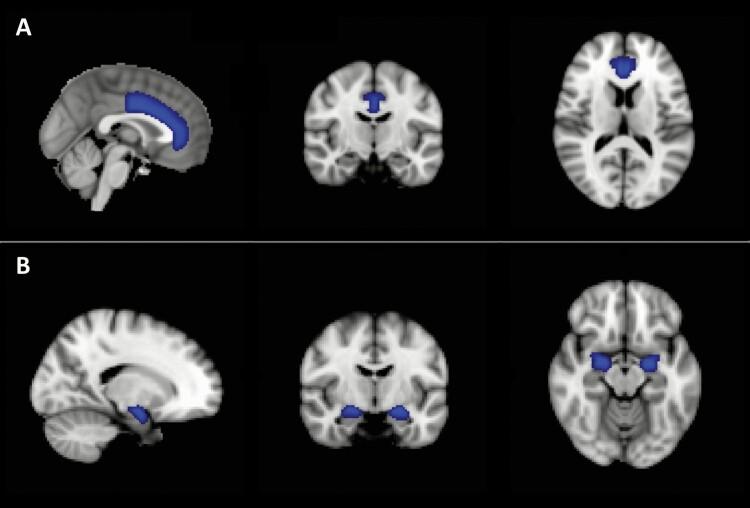

Participants consisted of youth, ages 13-20 years, including BD with OW/OB (BDOW/OB; n = 25), BD with normal weight (BDNW; n = 55), and normal-weight healthy controls (HC; n = 61). High-resolution T1-weighted and pseudo-continuous arterial spin labeling images were acquired using 3 Tesla magnetic resonance imaging. CBF differences were assessed using both region of interest and whole-brain voxel-wise approaches.

Voxel-wise analysis revealed significantly higher CBF in reward-associated regions in the BDNW group relative to the HC and BDOW/OB groups. CBF did not differ between the HC and BDOW/OB groups. There were no significant region of interest findings.